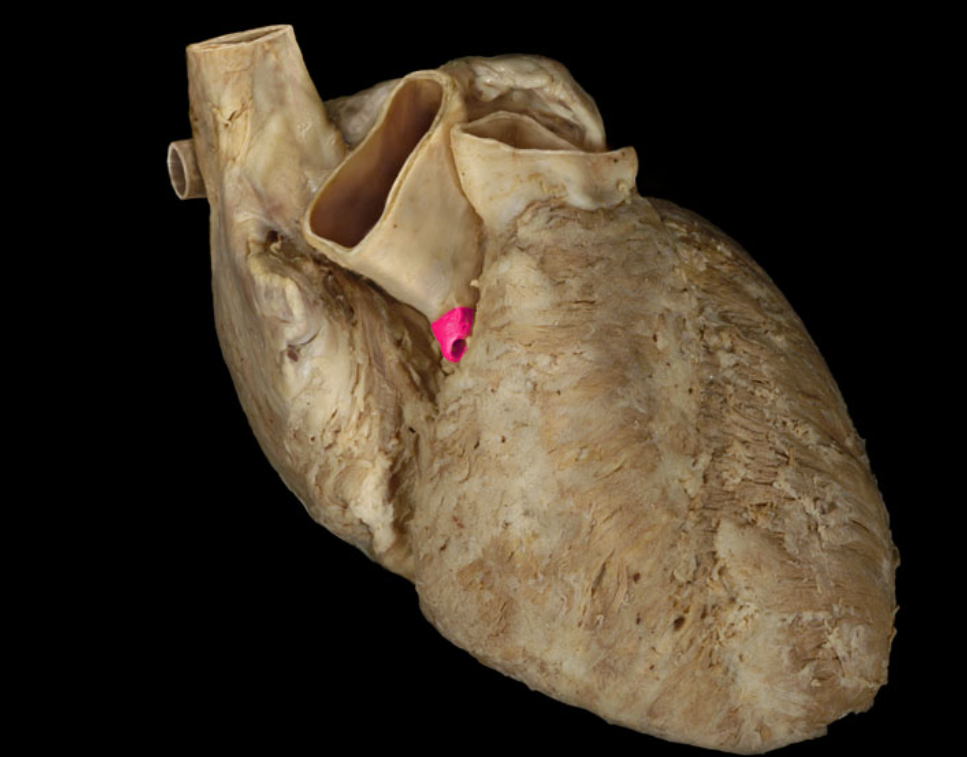

Aortic valve

Pulmonary valve